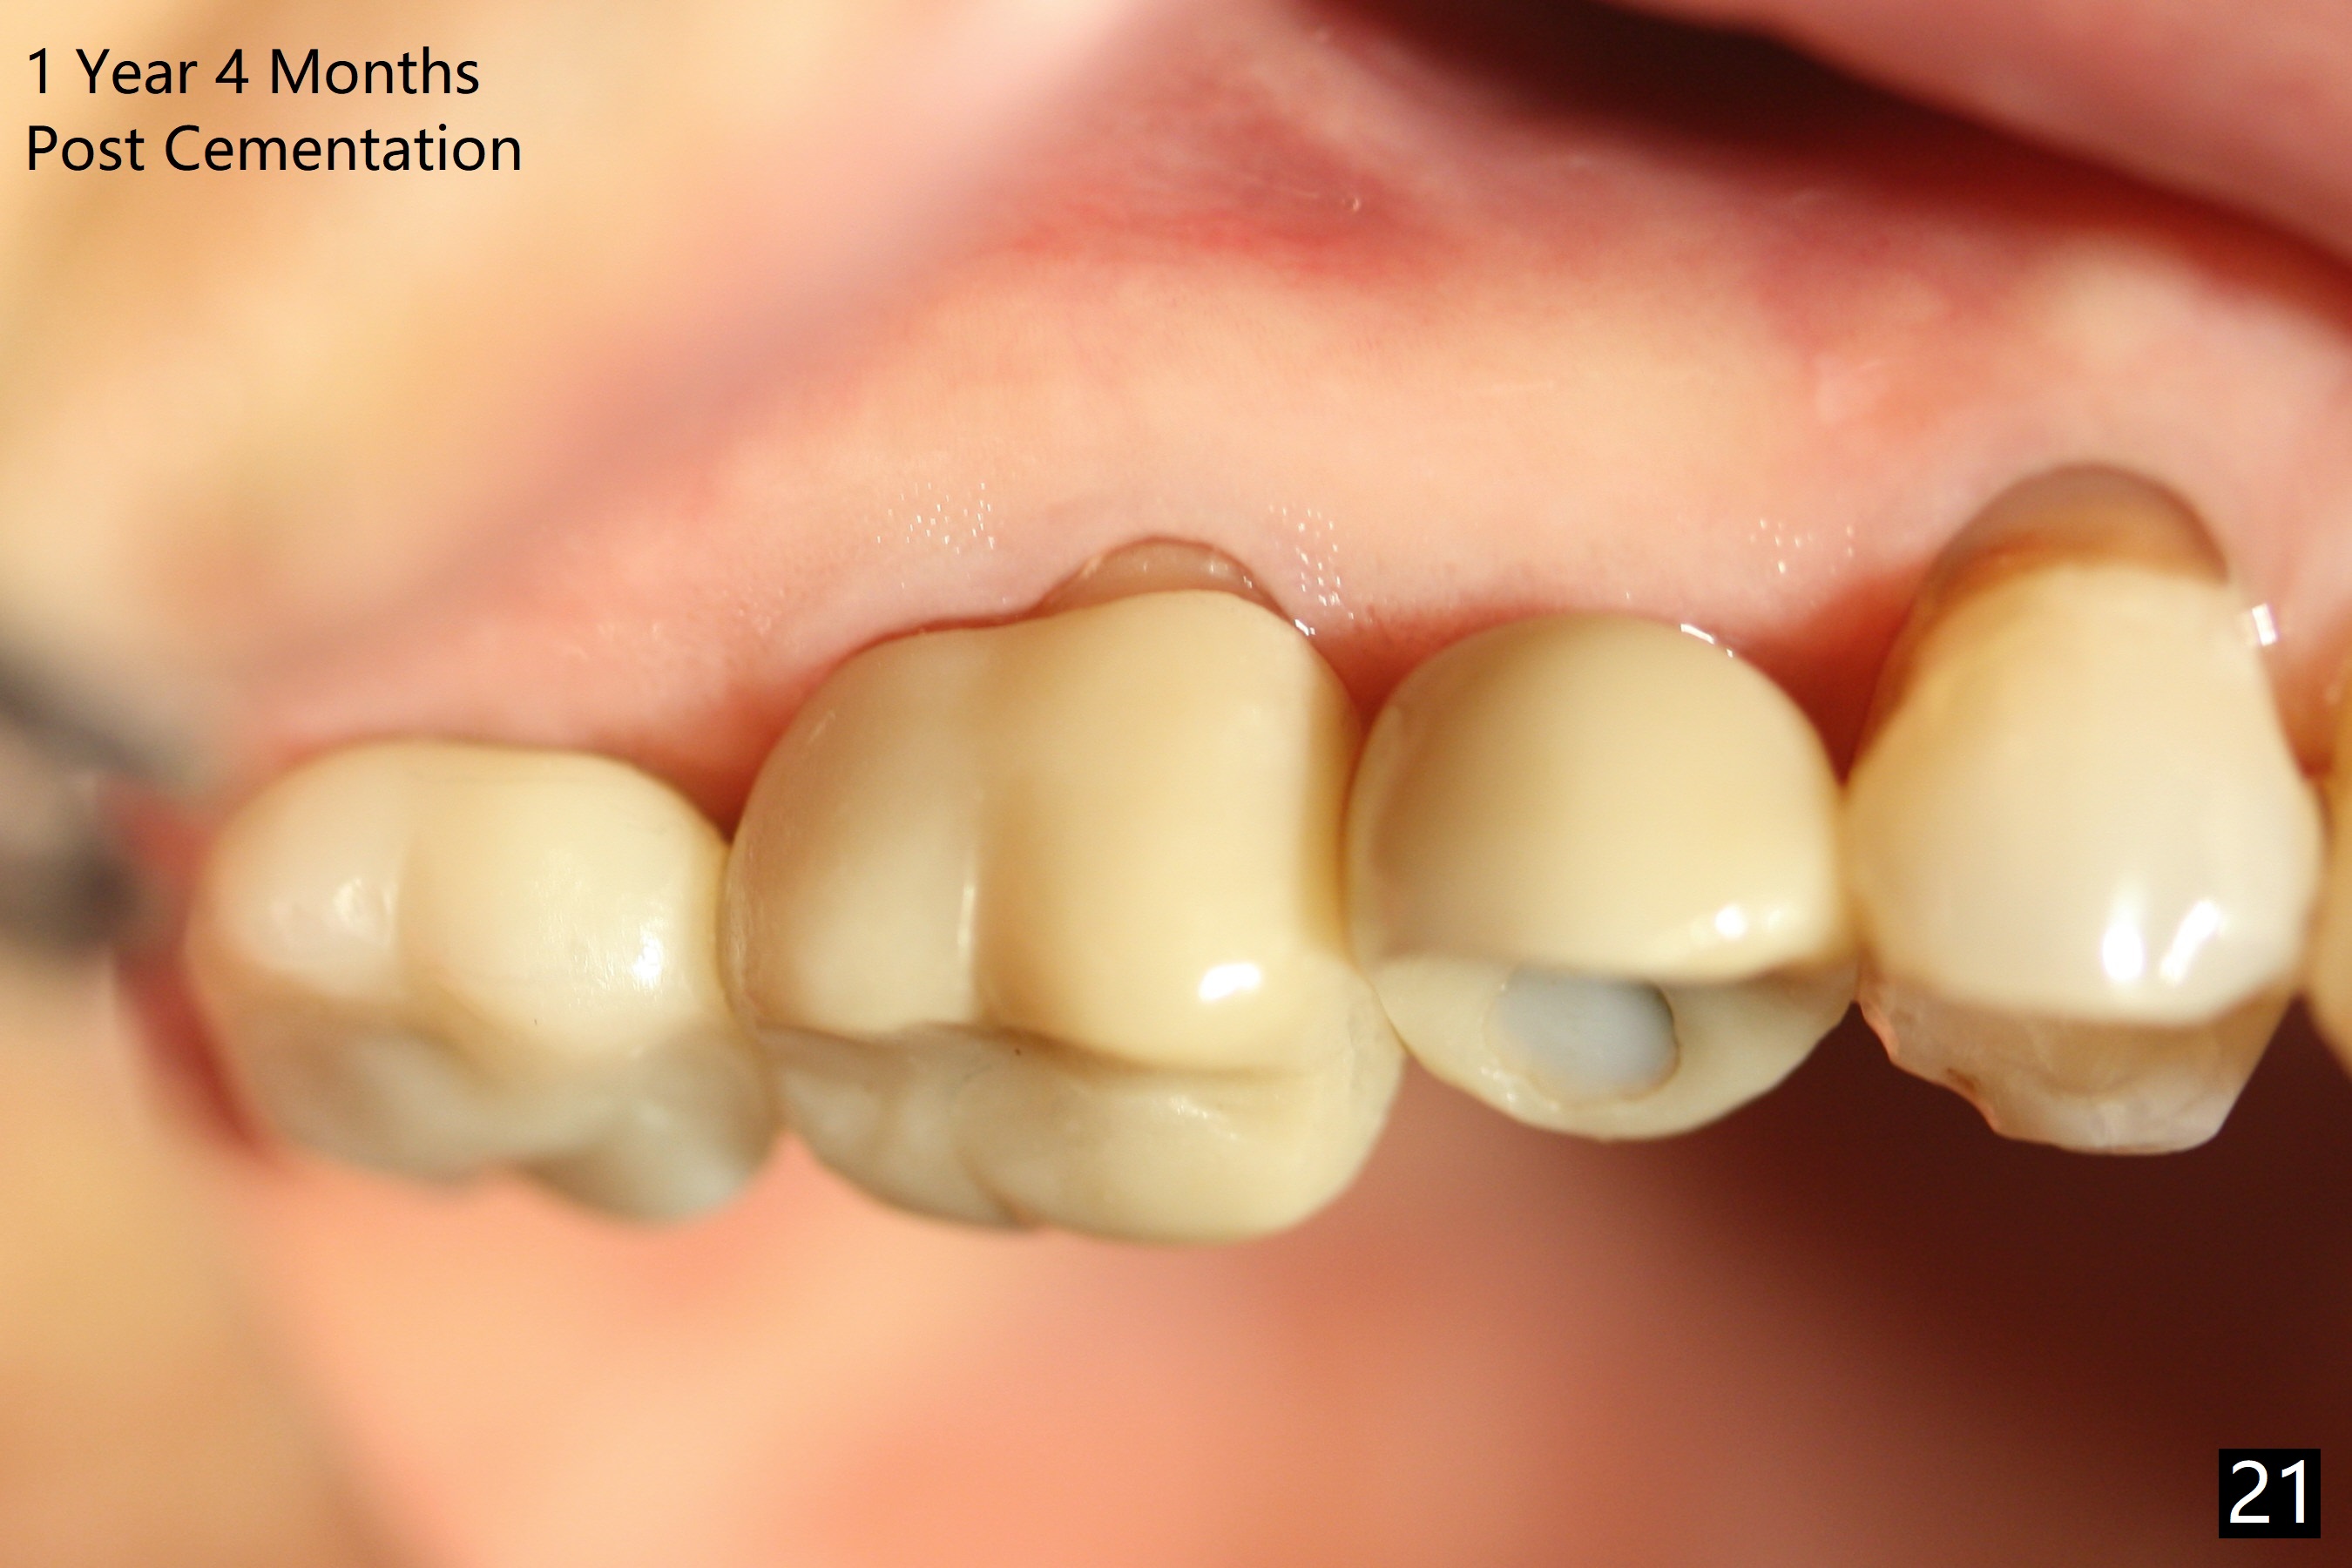

The right posterior final restorations (Fig.14) are fabricated as planned: increase in vertical height (Fig.15). The increase is minimal (Fig.14, 17(#2 limited crown height), 16 (#2 crown being thin *)). Fig.17,18 are taken immediately post cementation. There is no bone loss 10 months post cementation (Fig.19,20). The gingiva is healthy around the implant crowns (#2, 4 and 28) 1 year 4 months post cementation (Fig.21,22).